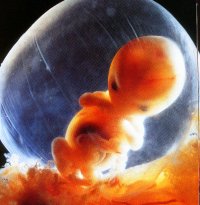

kb. így nézett ki,sajna nem kaptam képet,csak telóval fotóztunk!

kb. így nézett ki,sajna nem kaptam képet,csak telóval fotóztunk!